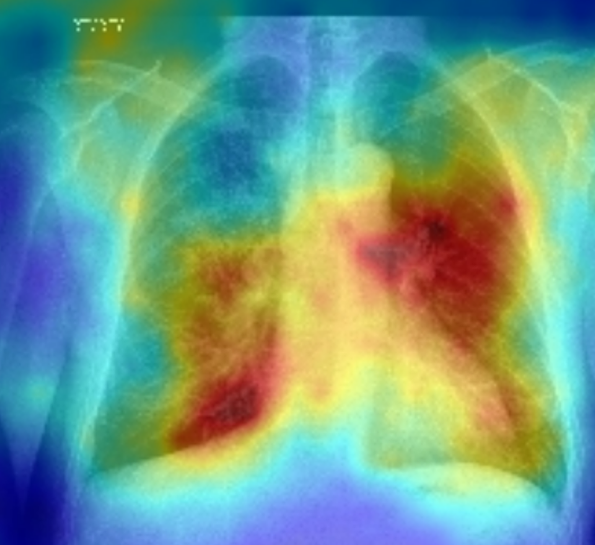

To delve deeper into the learned visual knowledge from IMITATE, we utilized Grad-CAM [57] to produce saliency maps for CXR images derived from the model in its pre-trained state. We select two CXR images showcasing two prevalent diseases, Edema and Lung Opacity. Notably, each of these images comes with ground truth annotation pinpointing the region of concern, as documented in [58]. As evident from Fig. 5, IMITATE boasts an impressive capability to accurately delineate the clinical regions of concern in the CXR images, outperforming its counterpart MGCA [4]. This is particularly noteworthy considering that IMITATE achieves this precision without relying on any external prompts or the need for additional model fine-tuning.